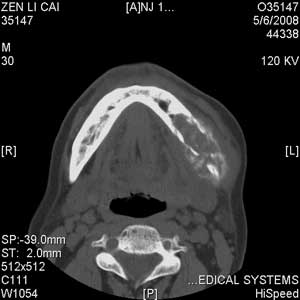

以下是引用jiangjing在2008-5-28 15:56:00的发言:[br]下颌骨左侧部骨质破坏,轻度膨胀,瘤骨形成,软组织肿胀考虑 恶性骨肿瘤-----肉瘤类